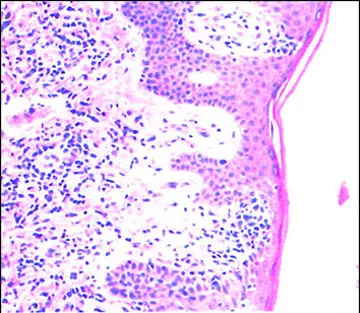

هماتولوژی - صفحه 10